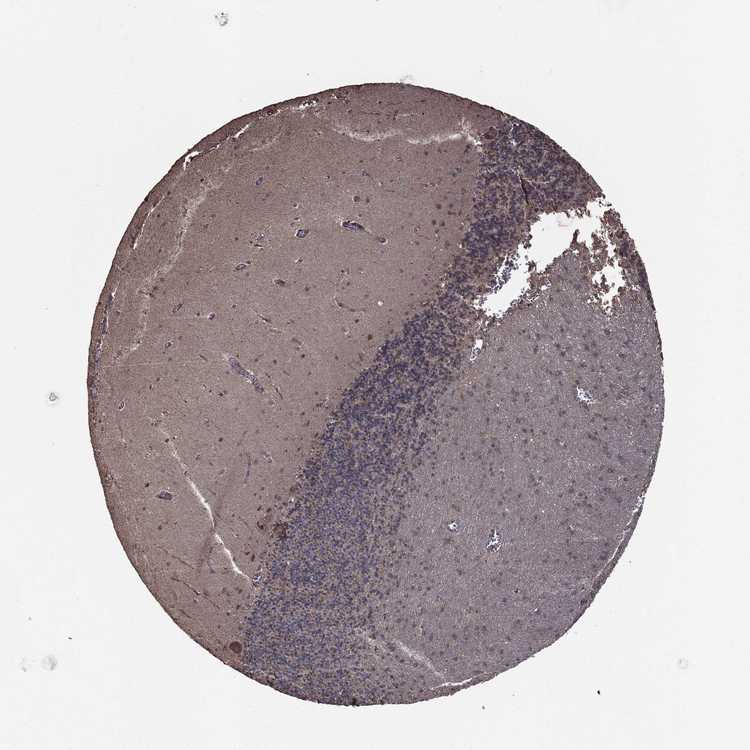

CEREBELLUM - Antibody stainingi

Antibody staining in the annotated cell types in the current human tissue is reported as not detected, low, medium, or high, based on conventional immunohistochemistry profiling in selected tissues. This score is based on the combination of the staining intensity and fraction of stained cells.

Each image is clickable and will lead to virtual microscopy that enables deeper exploration of all samples and also displays staining intensity scores, fraction scores and subcellular localization as well as patient and tissue information for each sample.

Antibody HPA074409

Purkinje cells Medium

Cells in granular layer Not detected

Cells in molecular layer Not detected